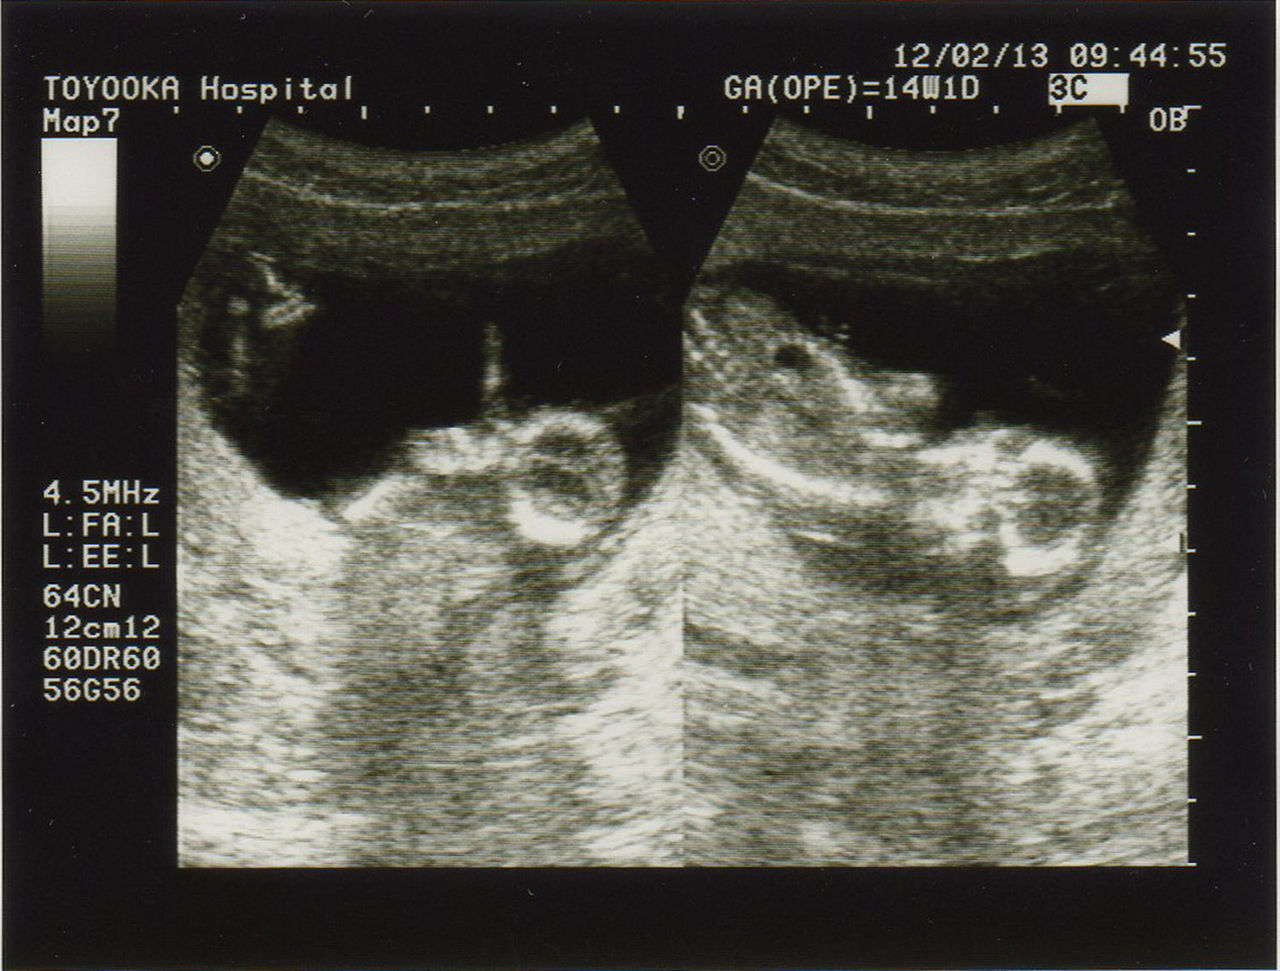

妊娠14週目の赤ちゃんの特徴 妊娠4ヶ月の第3週である「妊娠14週」は、妊娠中期の最初の週にあたります。 ママのおなかにすこし膨らみがみられるころですが、胎内で育つ赤ちゃんはどんな様子でしょうか。 赤ちゃんはどのくらいに成長しているの? 赤ちゃんの大きさ 15週目の終わりには、赤ちゃんは12センチくらいに、体重も50~70グラムくらいになります。りんごくらいの大きさだという人もいます。 肺 赤ちゃんは活発に羊水中を動き回りながら、羊水を鼻や上気道に取り入れ、肺胞の発達を促します。 妊娠14週の赤ちゃんの基礎情報 身長、BPD、体重、発達 妊娠14週(14w)は妊娠4ヶ月にあたり、胎盤がほぼできあがり、母体からの栄養が胎児に届けられるようになる時期です。 身体の重要な器官の形成が終わりに近づき、羊水を飲んで呼吸の練習をしたり、しゃっくりをしたりと動きが活発になりますよ。 この時期には、思考、知覚、記憶などをつかさどる「大脳

11妊娠14週の赤ちゃんの状態 妊娠14週では胎盤がほぼ完成に近づき、へその緒から栄養を吸収する準備が始まります。 赤ちゃんの内臓はほぼ完成し機能も発達し始め、体の見た目も人の形に近づいてきます。 腹部エコー検査の際には赤ちゃんの膀胱におしっこが貯まっている様子が見えたり、胃泡が見えることもあります。 赤ちゃんは自由に羊水内を動き回り妊娠3カ月(8週・9週・10週・11週) 妊娠4カ月(12週・13週・14週・15週) 妊娠5カ月(16週・17週・18週・19週) 妊娠6カ月(週・21週・22週・23週)妊娠14週目 赤ちゃんの成長とともに ママのお腹も妊婦らしく変化 胎動はまだ 生理のことから妊娠 出産 育児まで 女性のための情報サイト ルナルナ 妊娠14週 赤ちゃんのエコー写真 超音波写真まとめ たまひよ 妊婦健診 初3 赤ちゃんができた 妊娠14週目 s m0214

妊娠14週目エコー写真 胎児の大きさ お腹の張りは大丈夫 妊娠初期 All About

医師監修 妊娠14週のエコー写真 手足を動かす様子が見られる マイナビ子育て